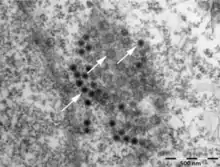

| Coltivirus virion.[1] | |

The Coltivirus virions are about 60-80 nanometers in diameter and are not enveloped, and are generally a spherical shape with icosahedral symmetry. Each virion has two concentric capsid shells surrounding a core of about 50 nanometers in diameter. The surface of the particle is relatively smooth.[7] The virus loses its infectivity when the surrounding fluid becomes acidic, around a pH of three, but is stable when the pH is between seven and eight. It also stops being a threat when the temperature becomes about fifty-five degrees Celsius.[7]